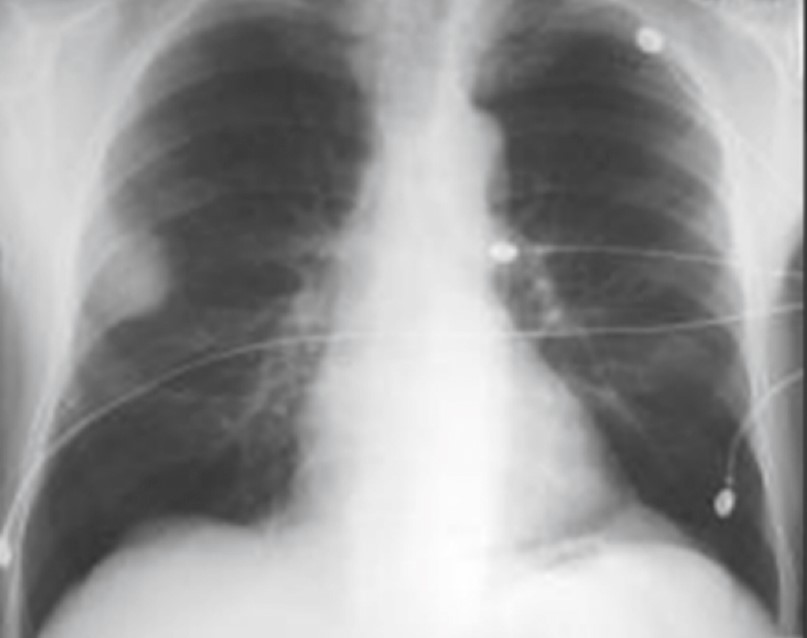

На рентгенограммах внутрибронхиальная липома проявляется весьма характерными признаками – ​спадением доли легкого вследствие обтурации соответствующего бронха. Чаще всего липомы локализуются в крупных бронхах – ​в долевом либо сегментарном. Диагноз липомы гистологически можно подтвердить после бронхоскопии, биопсии опухоли и тканевого исследования [34, 35]. Так, на рентгенограммах липома зачастую неотличима от центрального рака легкого (рис. 28-30).

Рис. 29. Эндобронхиально липома главного бронха слева